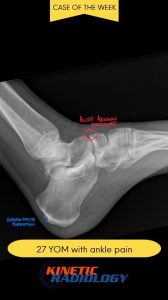

At Kinetic Radiology, we specialize in providing precise, comprehensive diagnostic imaging services tailored to the needs of healthcare professionals and patients. Led by board-certified Chiropractic Radiologists (DACBR), our team is committed to delivering clear, accurate reports that empower better healthcare decisions.

We are committed to enhancing patient care by delivering top-tier medical imaging evaluations and reports consistently. Our team of board-certified radiologists brings specialized expertise in diagnostic imaging, with a particular focus on chiropractic radiology that specializes in spine and musculoskeletal imaging. We strive to provide not just readings, but invaluable consultations, ensuring each patient receives the best that modern radiology has to offer. Our dedication to accuracy, speed, and reliability in off-site image interpretations sets us apart as trusted partners in healthcare.